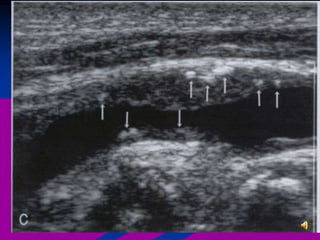

 Debemos localizar la

arteria vertebral (V).

 Se observa la arteria

vertebral interrumpida

por sombras acústicas

(S) generadas por las

apófisis transversas

adyacentes.